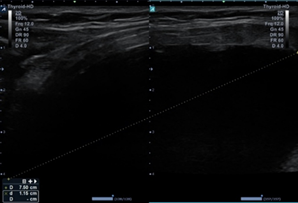

Baseline evaluation and ultrasound were

performed in the office (Figure 1).

a) Photo

b) Ultrasound image - AP and transverse view

c) Ultrasound image – lateral view

Figure 1: Baseline images before

intervention